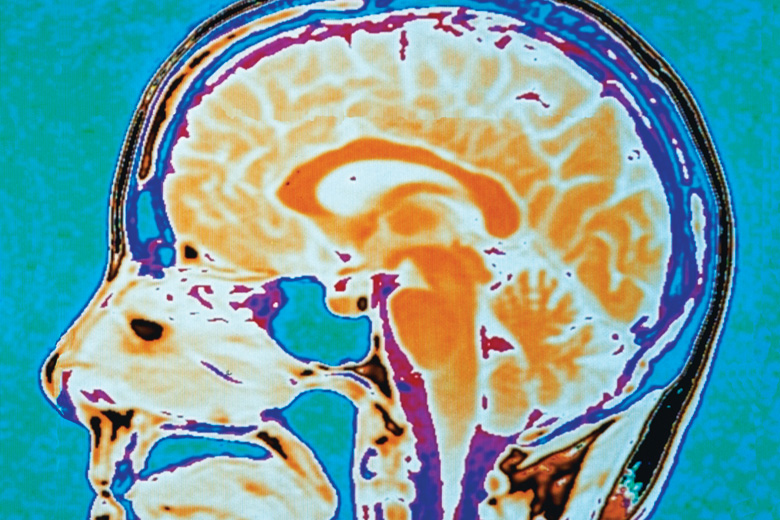

Close-up of human brain scan

Source:

Getty

The technologies are there, the problems to be addressed are tempting and the theoretical issues are profound, touching some of the deepest questions about what it means to be human